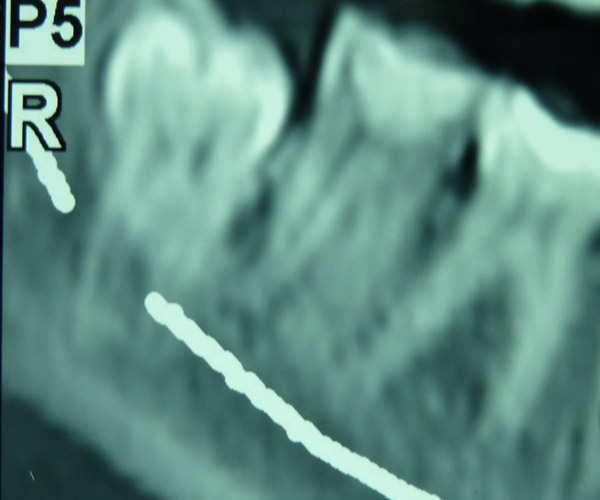

Dada su localización anatómica, en muchos casos el cordal se haya situado junto al nervio dentario, lo que aconseja un estudio radiológico preciso para situar con exactitud la relación entre cordal y nervio dentario.